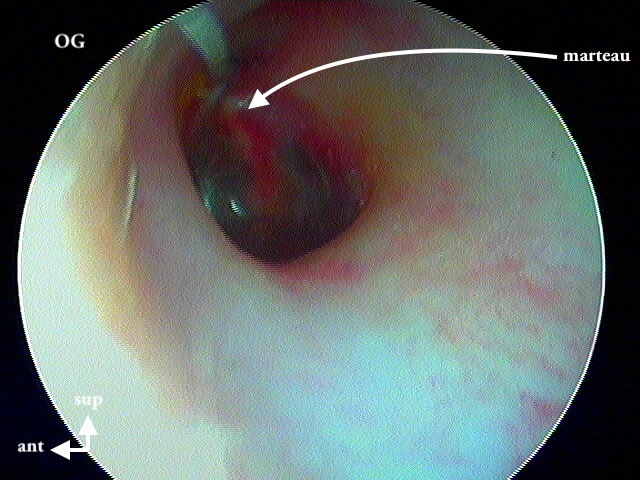

Pour connaitre le côté de l'oreille sur les photos, je m'aide du triangle lumineux antérieur mais aussi du marteau qui est une forme de nez de profil et me donne le côté de l'oreille.

OG normale